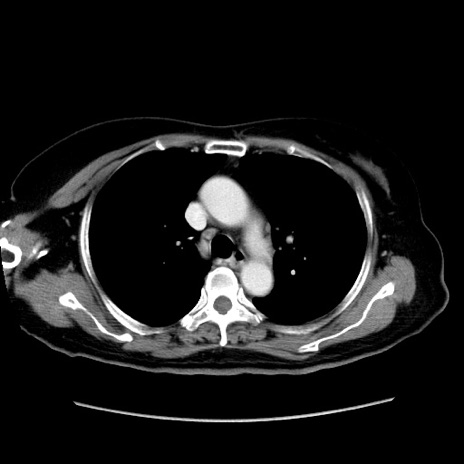

症例19(横断像)

【症例】80歳代女性

【主訴】下腹部痛

【現病歴】約8時間前より下腹部痛の出現あり、救急外来受診。

【既往歴】両側付属器切除

【身体所見】意識清明、下腹部正中に手術痕あり、その部位に一致して圧痛と反跳痛あり。腸蠕動音は亢進。

【データ】WBC 9300、CRP 0.15